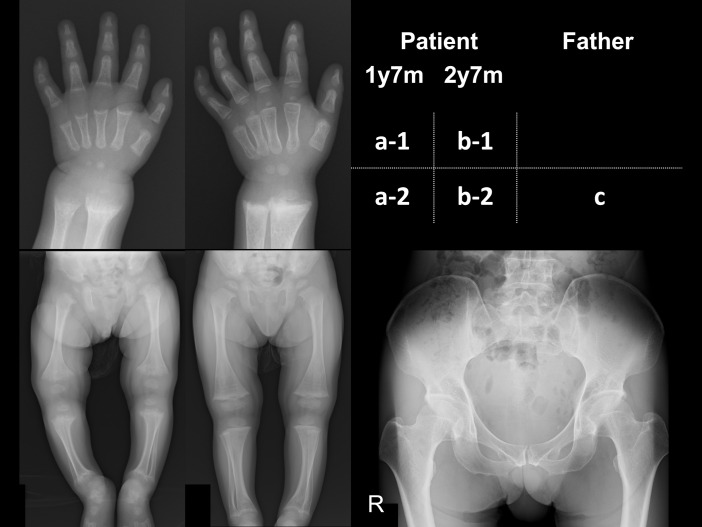

A case of autosomal dominant hypophosphatemic rickets.

常染色体显性低磷血症佝偻病1例。